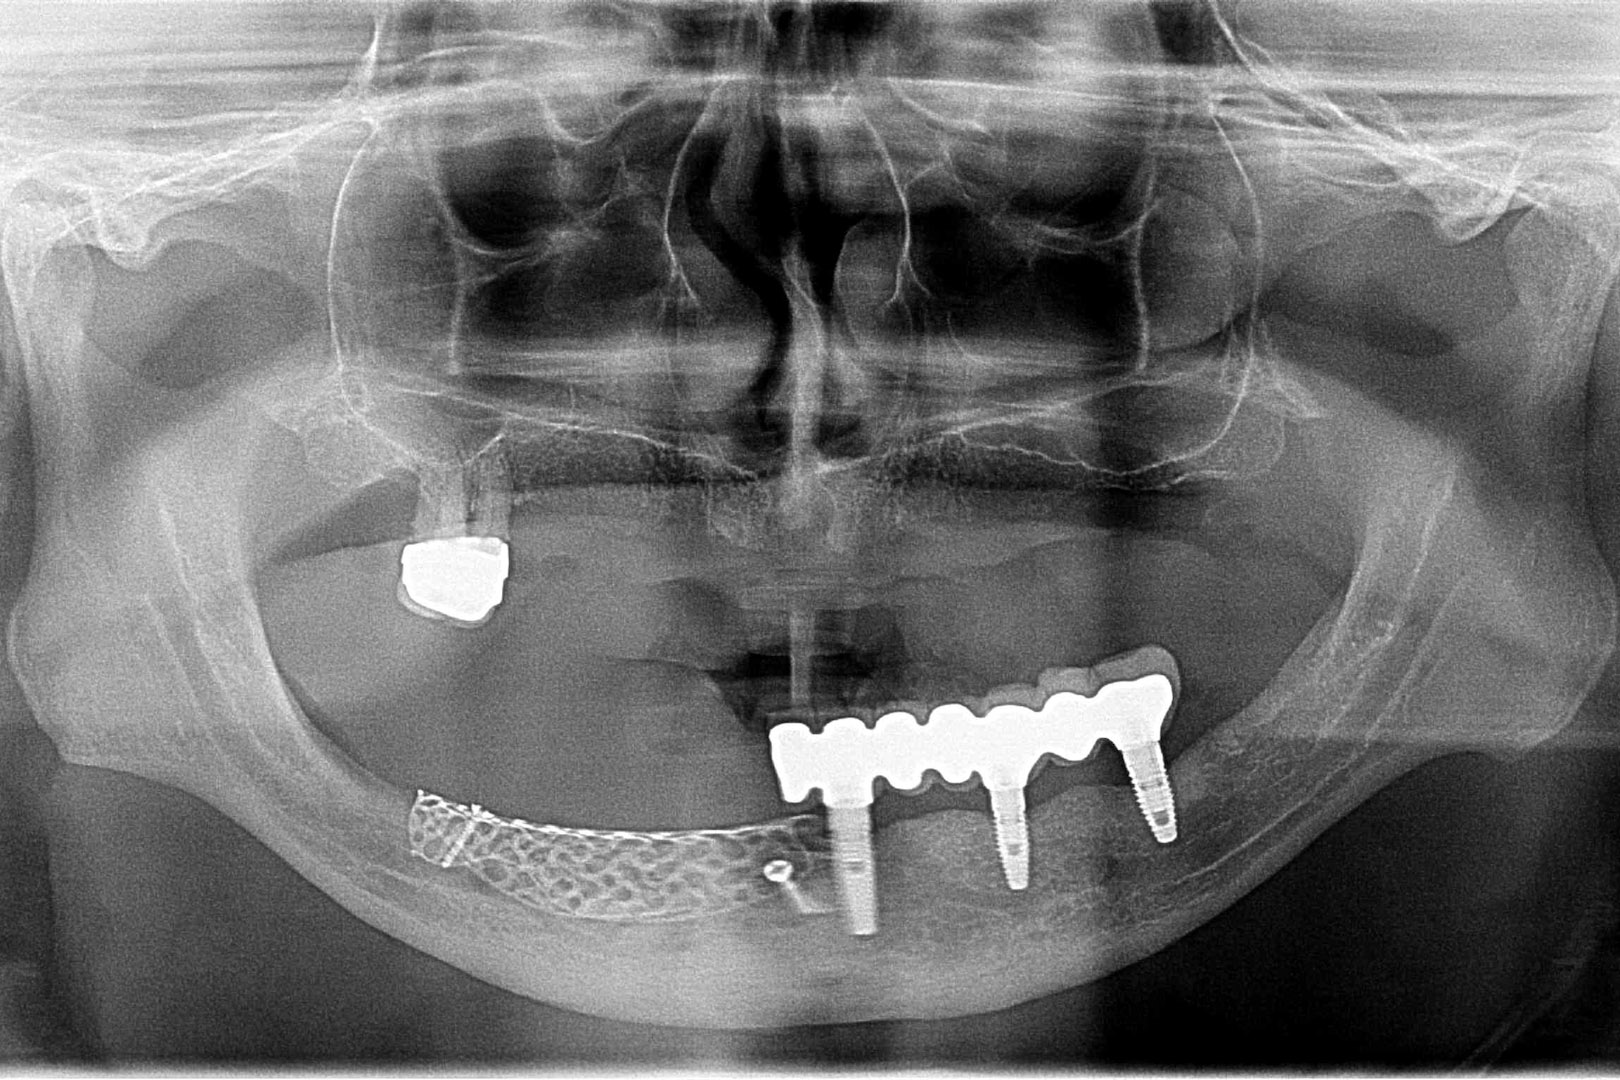

Przed podjęciem leczenia należy określić stopień zaniku kości szczęk oraz żuchwy. W tym celu przeprowadza się badanie kliniczne oraz odpowiednią diagnostykę obrazową pacjenta. Uwzględnia ona zdjęcie panoramiczne OPG jako podstawę dwuwymiarowego obrazowania podłoża kostnego oraz możliwe jest badanie tomograficzne CT lub bardziej precyzyjna tomografia stożkowa CBCT. Opcjonalnie wykorzystywana diagnostycznie tomografia pozwala na bardziej wnikliwą ocenę stopnia zaniku kości w trójwymiarowym, przestrzennym obrazie.

To kolejna metoda umożliwiająca precyzyjną odbudowę zadanego kształtu tkanki kostnej przy użyciu standardowych materiałów kościotwórczych, kości własnej lub PRF oraz zewnętrznego rusztowania w postaci siatki z biozgodnego stopu tytanu. Siatka jest indywidualnie projektowana w technologii CAD CAM i następnie drukowana dla konkretnego przypadku.

Dotychczas stosowane stabilizatory zewnętrzne w formie siatek tytanowych używane do regeneracji kostnej lub w zabiegach odtwórczych w chirurgii szczękowo-twarzowej uwzględniały materiały ręcznie doginane i formowane podczas zabiegu operacyjnego. Zastosowanie technologii CAD CAM dla potrzeb druku materiałów przeznaczonych do indywidualnej rekonstrukcji kostnej znacznie poprawiło precyzję i jakość uzyskiwanych efektów. Wdrożenie biozgodnych stopów tytanu do druku siatek zdecydowanie ograniczyło odsetek powikłań zapalnych.

Siatki stanowią stabilną obudowę – ograniczenie nadające kształt regenerowanej kości przy użyciu upakowanego pod nią materiału. Utrzymują i stabilizują rozdrobniony granulat kościotwórczy, co jest warunkiem prawidłowego procesu gojenia, jednocześnie nadając anatomiczny kształt i zakres odbudowie kostnej sprzed jej zaniku.

Precyzja projektu druku siatki bazuje na dokładności odwzorowania kształtu kości w stożkowej tomografii komputerowej CBCT, co zapewnia ich dobre przyleganie do podłoża kostnego oraz ogranicza powstawanie powikłań w postaci obnażania się siatek.

Precyzja projektu oraz materiał, z którego wykonana jest siatka (biozgodny stop tytanu), powodują, że obnażenie się siatki nie zaburza procesu gojenia i regeneracji kostnej. Wymaga jedynie większej ilości kontroli pozabiegowych oraz wzmaga czujność higieniczną zarówno ze strony lekarza, jak i pacjenta.

Ten rodzaj odbudowy kostnej stosowany jest w sytuacjach złożonych, trójwymiarowych 3D ubytków kości, przy których standardowe metody odbudowy są niewystarczające. Ilość kości, którą możemy uzyskać, stosując tę metodę, to nawet kilka centymetrów sześciennych.

Metoda rekonstrukcji kostnej w oparciu o indywidualnie drukowane siatki z tytanu dla implantacji wszczepów śródkostnych stosowana jest najczęściej jako dwuetapowa. W pierwszym etapie odbudowywana jest kość, natomiast implanty wszczepiane są po okresie 4–6 miesięcy. Na wgojenie implantów oczekujemy od 4 do 6 miesięcy w zależności od miejsca ich lokalizacji. Siatka tytanowa po spełnieniu swojej funkcji rusztowania dla odbudowującej się kości jest następnie usuwana w dniu wszczepienia implantu. Jeżeli kość spełnia odpowiednie warunki, istnieje możliwość zastosowania modyfikacji siatki tytanowej, która umożliwia jednoczesne wprowadzenie implantów wraz z odbudową kostną. Wariant ten skraca czas od pierwszego zabiegu do wykonania gotowych koron protetycznych na wprowadzonych implantach.